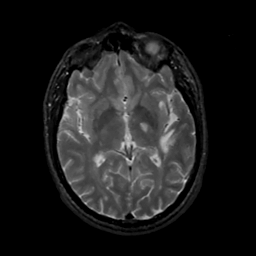

MR Study #15, June 9, 1991 -- Slice #25